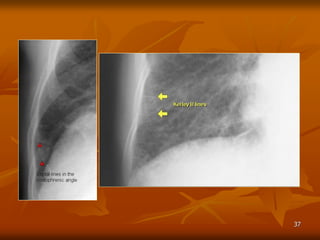

CARDIAC FAILURE

-Enlarged heart size.

-No clear heart border (interstitiel

edema), Kerley’s line, pleural

effusion.

-Redistribution.

37

Dày vách liên tiểu thùy